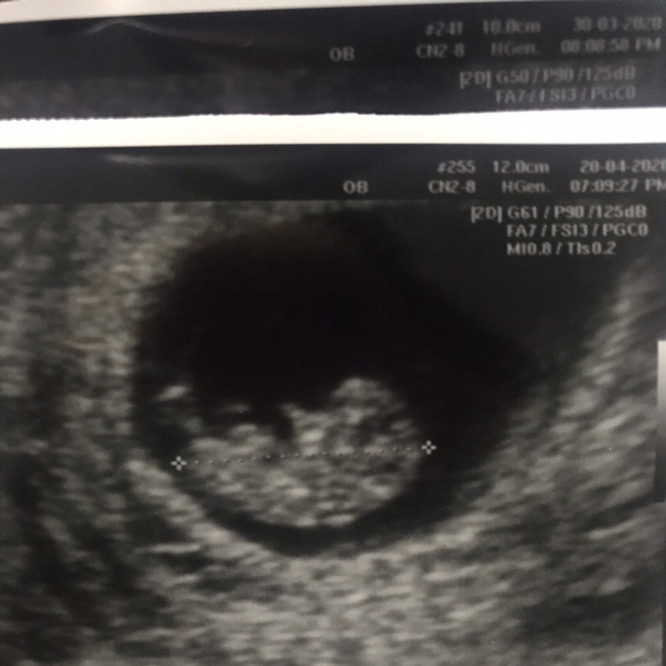

ตอน 11w น้องมีอวัยวะครบหมดแล้ว และดิ้นอย่างแข็งแรงเลยค่ะ

ของเรา 11 สัปดาห์ตอนนี้ 18 วีค 5 วันแล้ว ไปหาหมอพรุ่งนี้จ้า